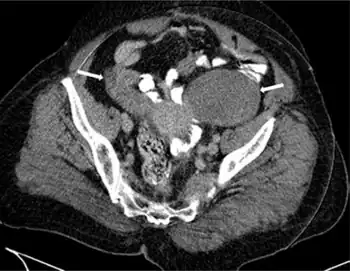

Krukenberg tumors often come to the attention when they cause abdominal or pelvic pain, bloating, ascites, or pain during sexual intercourse. Krukenberg tumors can occasionally provoke a reaction of the ovarian stroma which leads to hormone production, that results in vaginal bleeding, a change in menstrual habits, or hirsutism,[3] or occasionally virilization[4] as a main symptom. In rare cases the disease can manifest with hydronephrosis and hydroureter.[5]

All these symptoms are non-specific and can also arise with a range of problems other than cancer, and a diagnosis can only be made following confirmatory investigations such as computed tomography (CT) scans, laparotomy and/or a biopsy of the ovary.

In terms of the diagnosis of krukenburg tumors the following is done:[8]

- CT scan

- Ultrasound

- CA-125 Test (elevated)